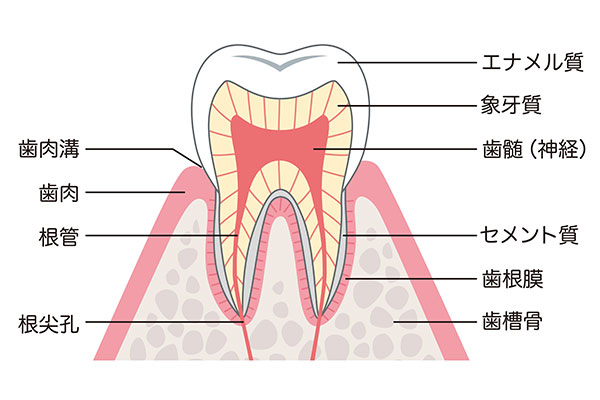

歯の神経(歯髄)とは

歯の中には、神経や血管が束になった歯髄という組織があります。この神経(歯髄)には、歯に栄養を供給し、健康を保つ重要な役割を持っているため、むし歯が進行して神経を取ることになってしまうと、歯はもろくなり、破折のリスクが高まります。また、神経がなくなってしまうと、歯の異変を感じることができなくなるなど、歯の寿命に大きく影響します。

当院は、むし歯が進行して神経に近づいた場合でも、できる限り神経を残すよう努めます。深いむし歯の治療では、手用のエキスカベーターを使用し、必要な部分だけを慎重に取り除きます。また、神経が露出してしまった場合でも、覆髄 という処置を行い、神経を保護することを検討します。当院では、MTAセメントを使用し、神経の保存をサポートします。MTAセメントは湿度が高い環境でも高い効力を発揮することができ、殺菌力や封鎖性が高いため、再感染のリスクを大きく軽減することが期待できます。

むし歯が進行し、歯の神経が細菌感染してしまった場合、神経を取り除く 根管治療 が必要になります。根管治療では、感染した神経や歯質を取り除き、歯の内部をしっかりと消毒・封鎖することで、歯を残すことを目的とします。